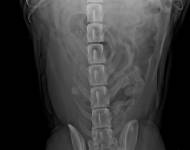

MVDr. Meloun: Lumbosakrální přechodový obratel